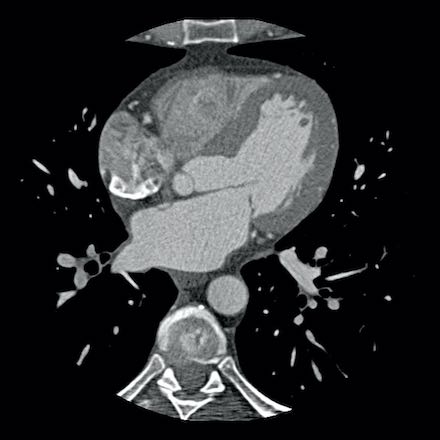

case 1 – CAD-RADS 2/P1

First, scroll through the scan.

Not all images are included. Some images without any abnormalities are skipped

from the series.

How would you describe the findings on the coronary CTA?

The findings are:

- Agatston score of

this patient was 14 (P1). Please, also note the calcification of the aortic valve. - Some partially

calcified and calcified plaques are present in the LAD with mild stenosis

(25-49%). - Calcified-plaque in

the LCX causing minimal stenosis (<25%). - Non-calcified

plaque in the distal RCA causing minimal stenosis (<25%). - This patient classifies

as CAD-RADS 2/P1, which means no further workup is needed.